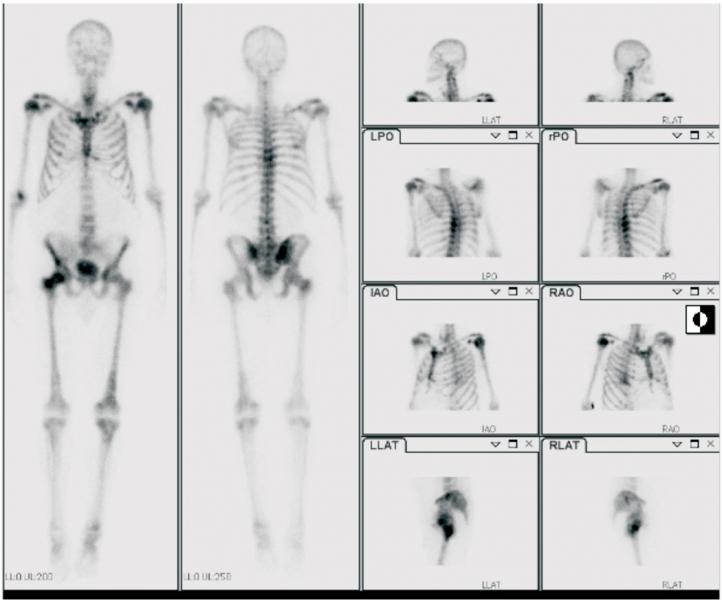

Whole-body 131I imaging in a 52-year-old woman with papillary thyroid cancer post thyroidectomy. Radiotracer uptake in the neck is seen at sites of residual malignant disease. 131I was subsequently given to ablate the residual sites of malignant disease.

Indeed, physicians have been imaging and treating patients with thyroid disease using radioactive iodine since 1946.2 The first use of iodine-131 (I-131) radioimmunotherapy occurred in 1982.3 Theranostics is a process of therapy for individual patients where treatment can be tailored based on imaging results using the same molecule and targets on tumor cells. Using the same or similar radiopharmaceutical for both imaging and therapy provides the opportunity to image disease sites that will be targeted both before and after therapy. It also provides the possibility of seeing what will be treated, estimating the amount of radioactivity that will be taken up at sites of disease versus the amount that will be taken up by normal tissue and calculating the specific amount of radioactivity needed to achieve maximum efficacy with limited toxicity. Figure 1 shows an image of a patient with thyroid disease who was imaged and treated using I-131.

The first trial of an α emitter in TRT was reported in 1997.9 Although TRT has been used for the palliation of patients with metastatic prostate cancer to bone for several years, Ra-223-dichloride (Xofigo; Bayer Healthcare Pharmaceuticals) was the first radiopharmaceutical shown to extend life in men with castration-resistant disease.10 Indeed, since FDA approval for the use of Xofigo in men with castration-resistant prostate cancer was obtained in 2013, this has become increasingly prevalent in routine oncologic clinical practice as a way to target and treat bone metastases. Figure 2 shows a patient with prostate cancer and widespread bone metastases.